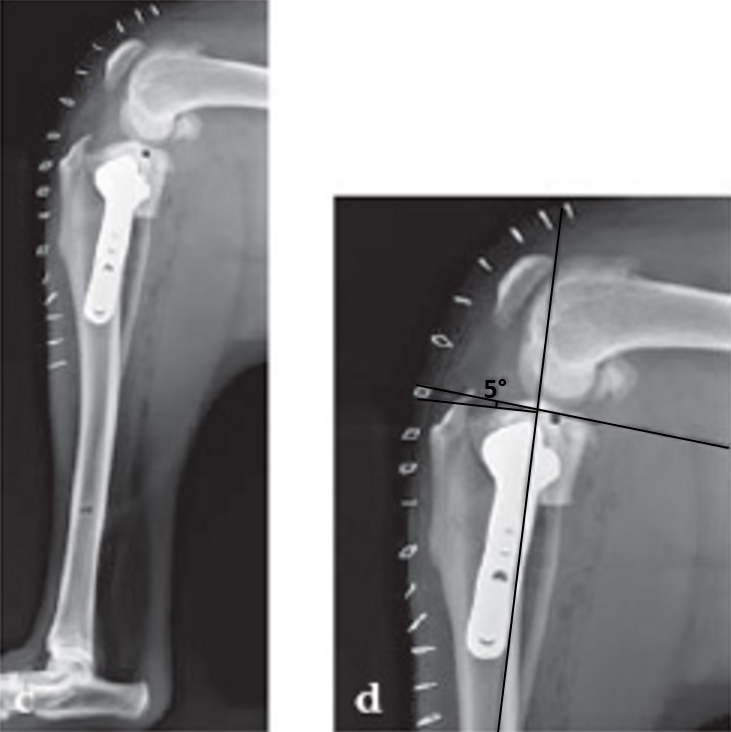

Case 4: Three-year-old neutered female Tosa, 60 kg, chronic (6 months) lameness, painful stifle.

(Case provided by Randy Boudrieau, North Grafton, USA)